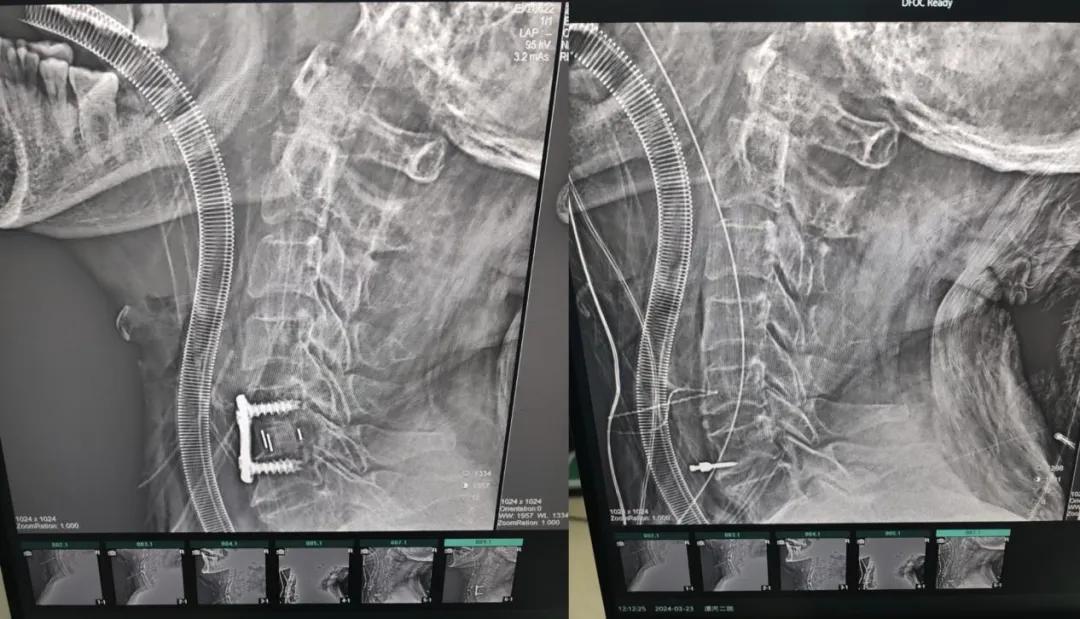

近日,70歲的馬阿姨,因摔傷后出現(xiàn)持續(xù)性頸部疼痛伴右側(cè)肢體無(wú)力、麻痛,影響日常生活。于是來(lái)到市二院神經(jīng)外科就診,經(jīng)檢查發(fā)現(xiàn):頸椎MR示:頸3/4、4/5、5/6、6/7椎間盤(pán)變性突出(中央型)并繼發(fā)性椎管變窄,頸椎退行性改變,頸5椎體水平頸髓水腫。神經(jīng)外科副主任劉沛濤根據(jù)患者癥狀、體征、影像學(xué)三者結(jié)合診斷為“脊髓型頸椎病”,考慮到患者癥狀逐漸加重、保守治療效果不佳等情況,建議盡快手術(shù)治療。

經(jīng)過(guò)縝密的術(shù)前準(zhǔn)備和手術(shù)計(jì)劃,在鄭大一附院神經(jīng)外科張風(fēng)江教授的指導(dǎo)下,神經(jīng)外科團(tuán)隊(duì)順利為患者實(shí)施“顯微鏡下頸椎前路C5/C6椎間盤(pán)切除椎間融合+內(nèi)固定術(shù)”,手術(shù)時(shí)間不到1小時(shí)。術(shù)后患者恢復(fù)情況良好。